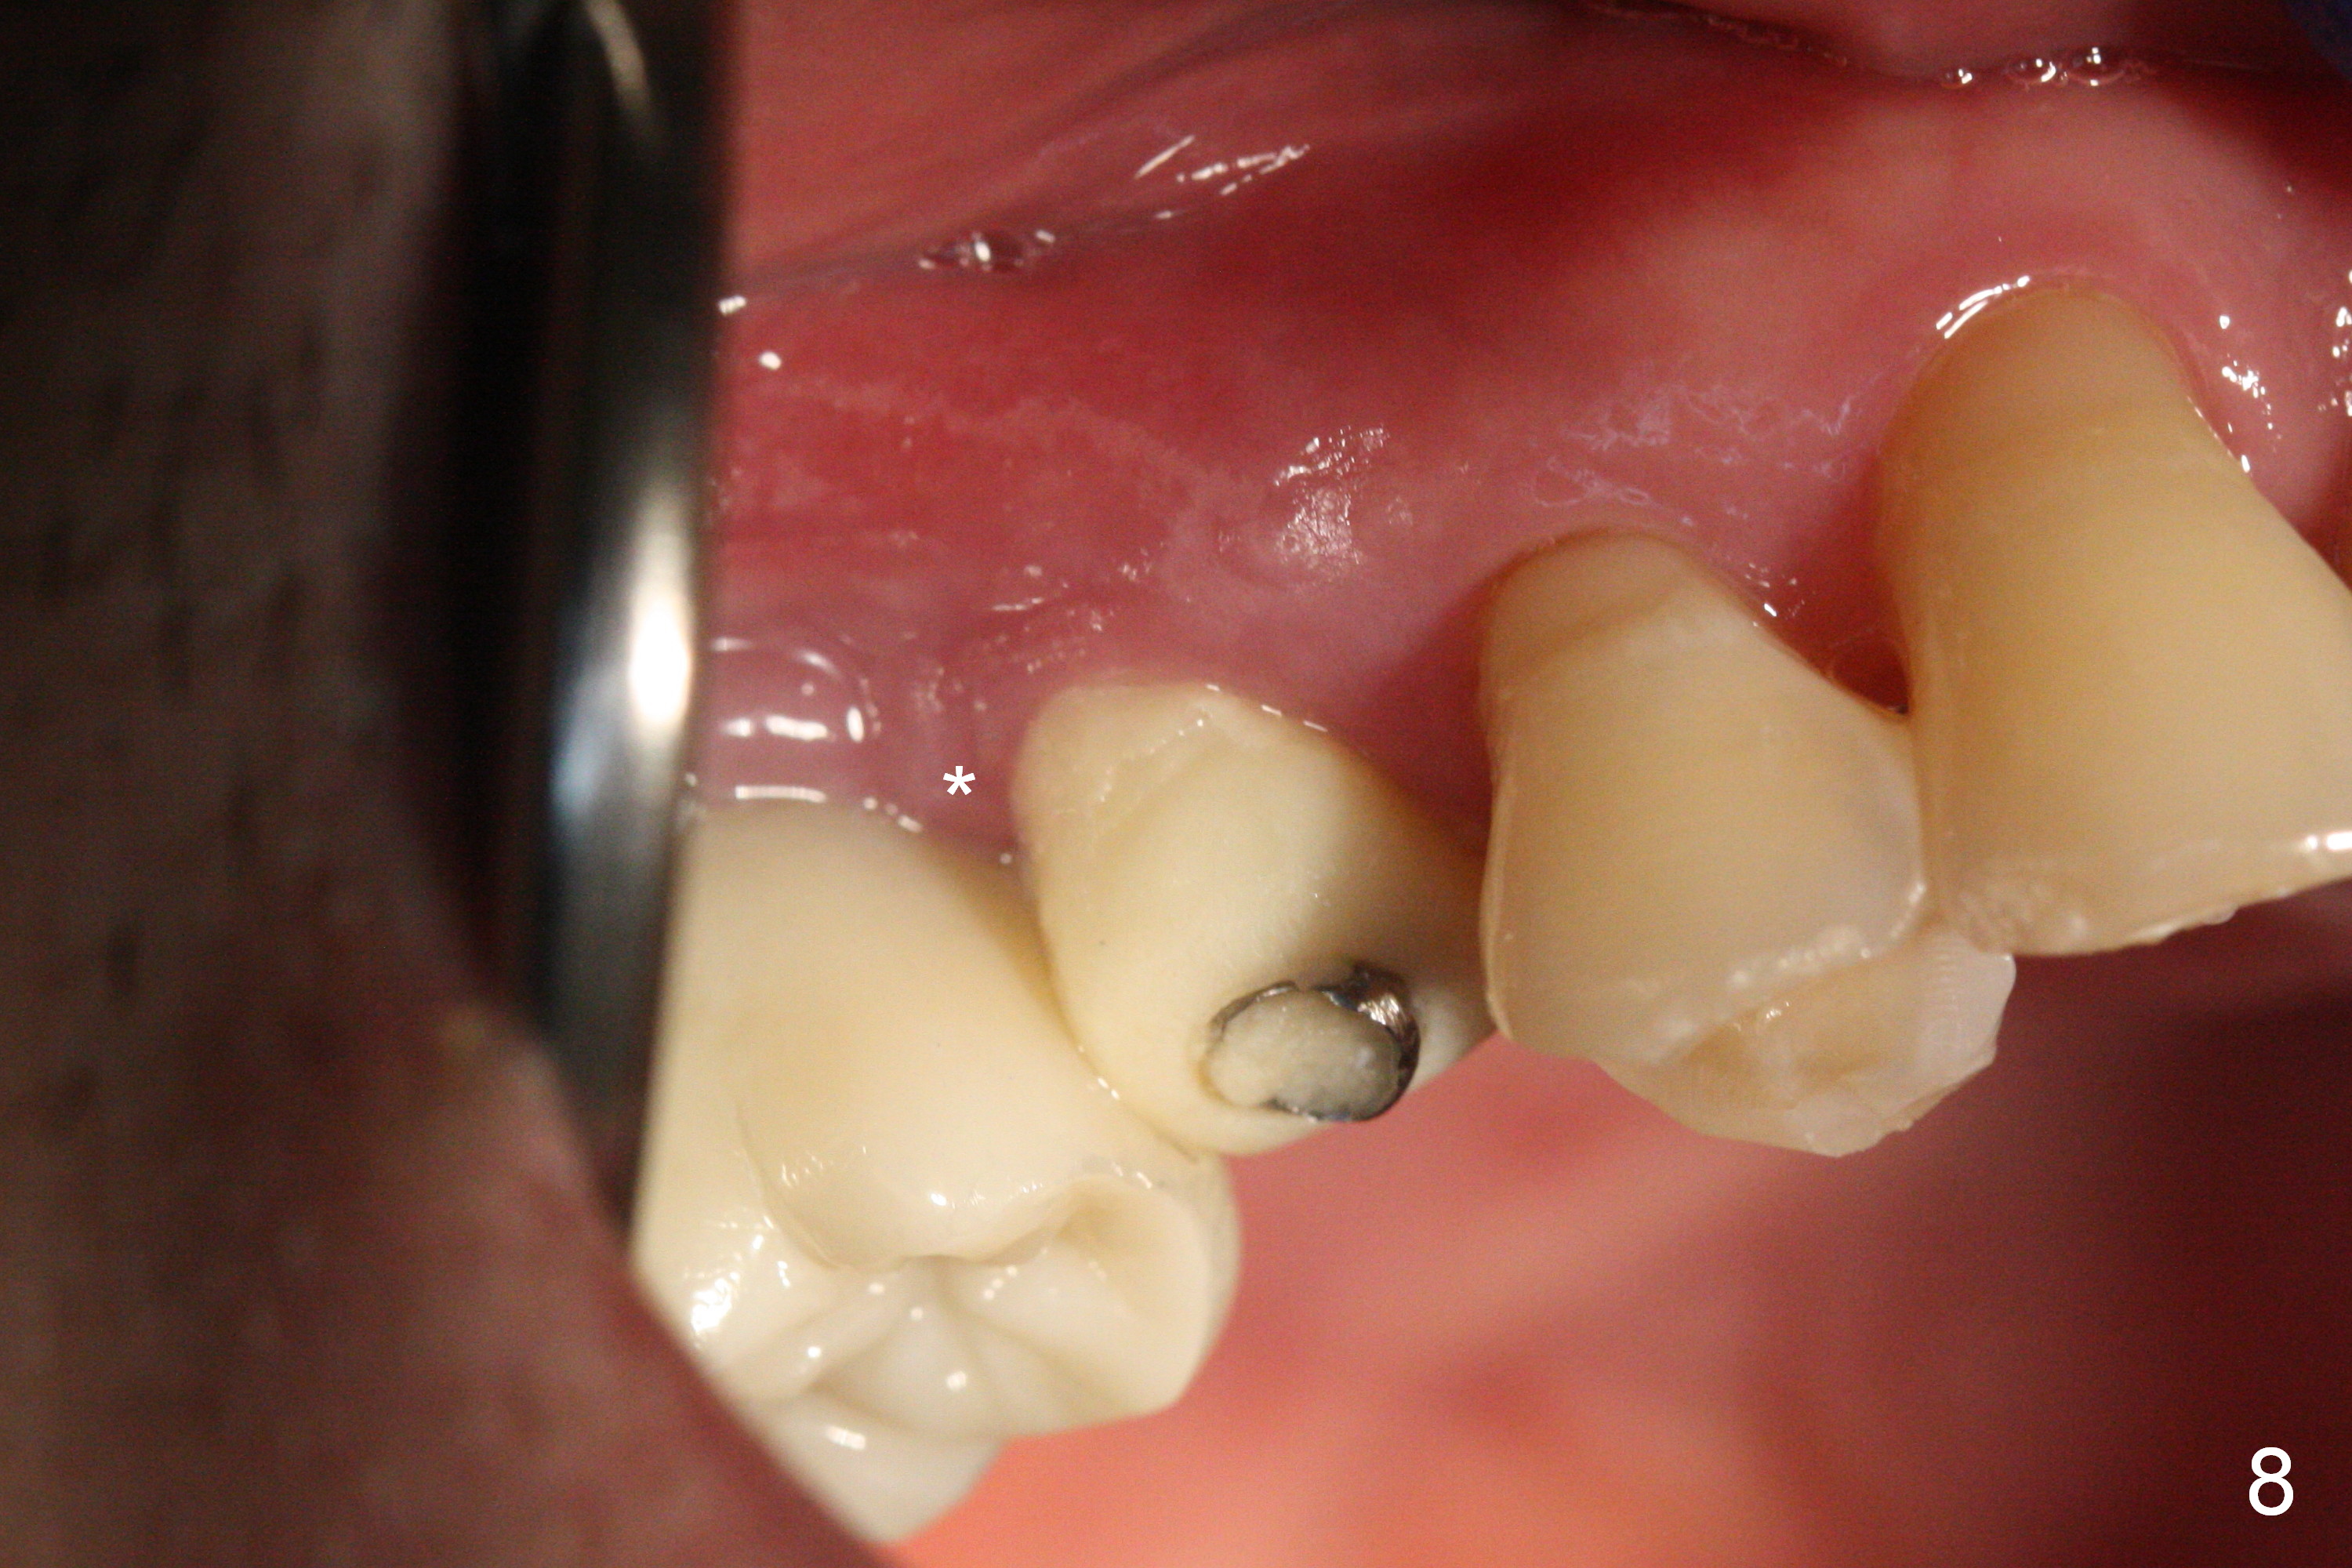

The distal papilla reforms buccally (Fig.8 *) and palatally (Fig.9) 4 months postop. It appears that the 4 mm cuff of the pair abutment (Fig.10 >) is apical to the mesial crest (*). The distal coronal implant threads seem to be covered by bone graft (Fig.11 <). Therefore pair abutments with 5 mm or more cuff are required in cases of the uneven bone. Implants have to be placed deep. CT taken 3 months post cementation (10 months postop) shows that the implant is placed in the middle of the alveolus without apparent thread exposure. CT taken 1 year and 8 months post cementation (Fig.13) shows that the implant is placed in the middle of the alveolus without apparent thread exposure, as compared to those at #2 and 3, which are placed buccal (B).